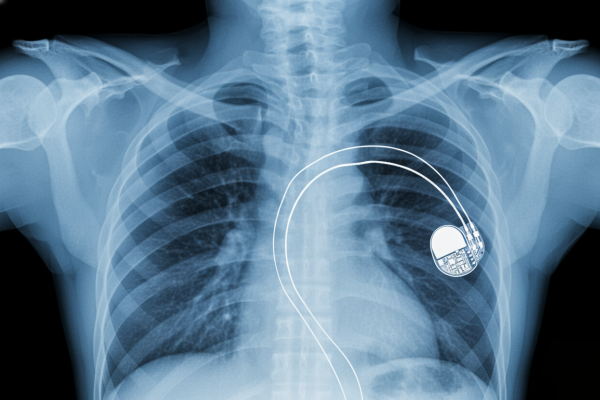

pacemaker ph pinterest

Non è la sceneggiatura di un thriller, ma una possibilità concreta della nuova era digitale: un omicidio condotto tramite rete wireless. L’arma del delitto? Un dispositivo progettato per salvare vite. La minaccia di hackerare un pacemaker non è più fantascienza.

Dal salvavita alla minaccia invisibile

Per lungo tempo, pacemaker, defibrillatori impiantabili (ICD) e pompe di insulina erano sistemi chiusi, isolati dal mondo esterno. Ora, invece, sono “smart”: dotati di connettività Bluetooth o a radiofrequenza che consente ai medici di monitorare il paziente a distanza.

Un progresso straordinario, ma anche una porta d’ingresso per gli hacker. Un esperto con un’antenna e le giuste competenze può intercettare il segnale del dispositivo persino dall’altra parte di un edificio o da un’auto parcheggiata. Una volta stabilito il collegamento, ottiene il pieno controllo del cuore della vittima.